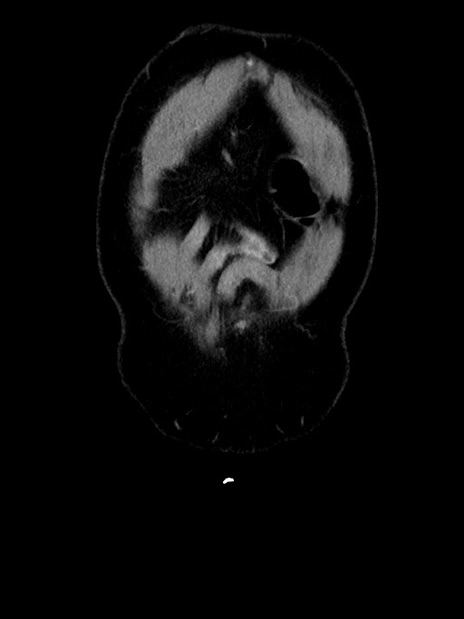

横断像

【症例】70歳代 男性

【主訴】腹部膨満、嘔吐

【現病歴】昨日より腹部膨満感出現。本日増悪し、仙痛出現。嘔吐あり、受診。

【既往歴】糖尿病、胆摘後

【身体所見】BP 149/80mmHg、HR 74/min、BT 35.9℃、腹部:膨満、軟、圧痛なし。腸雑音減弱あり。上腹部正中切開瘢痕あり。

【データ】WBC 13500、CRP 1.72